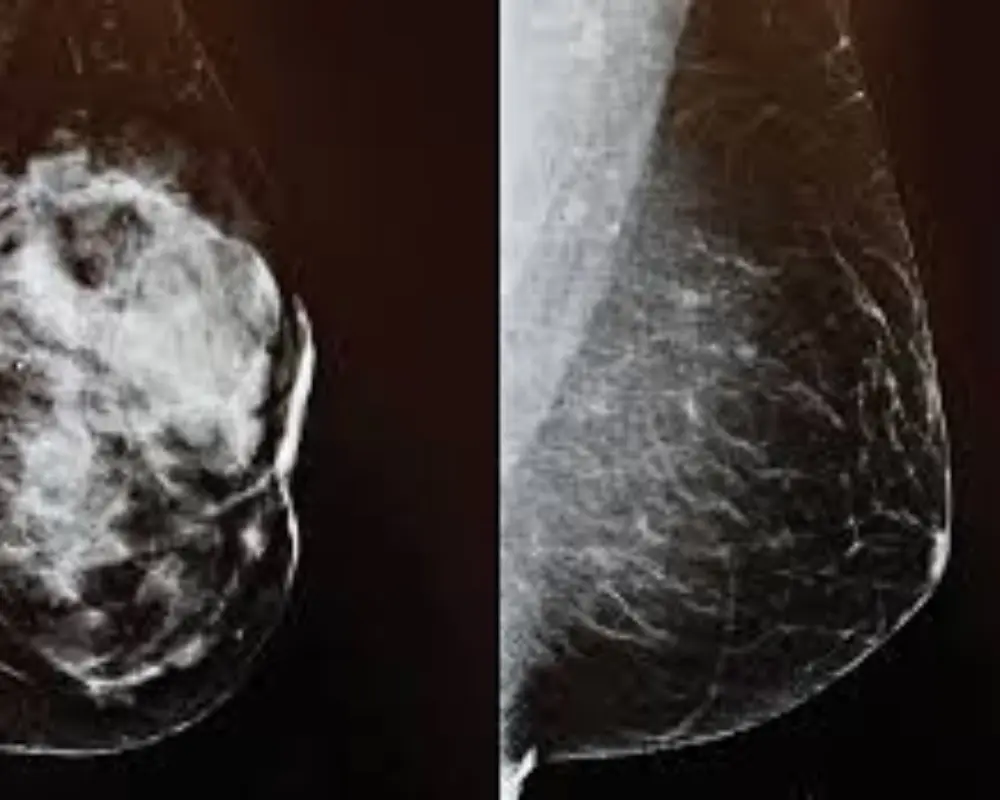

Dense Breast Tissue

Breast MRI is commonly used for dense breast tissue evaluation, where mammograms may be less effective. It helps provide clearer imaging and improves detection of abnormalities that might otherwise go unnoticed.

Unclear Mammogram

Breast MRI is often used when mammogram results are unclear or inconclusive. It provides additional imaging detail to better evaluate suspicious areas and helps determine whether further testing or treatment is needed.

Patients with unclear or abnormal mammogram results may need a breast MRI to provide clearer imaging, helping evaluate suspicious areas and support accurate diagnosis and next care decisions.